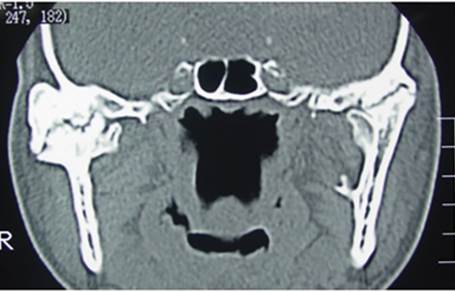

We asked him to get a preliminary CT scan to confirm our suspicion that showed a classical picture of fusion of the joint to the skull base.

In the CT scan image shown here, you can see a large boulder-like enlargement of the joint. This is the ankylotic mass.

Data acquisition- This is the first step in the process. It includes taking high resolution CT images to obtain an accurate joint picture and intraoral dental scans to get an accurate depiction of the patient’s bite.